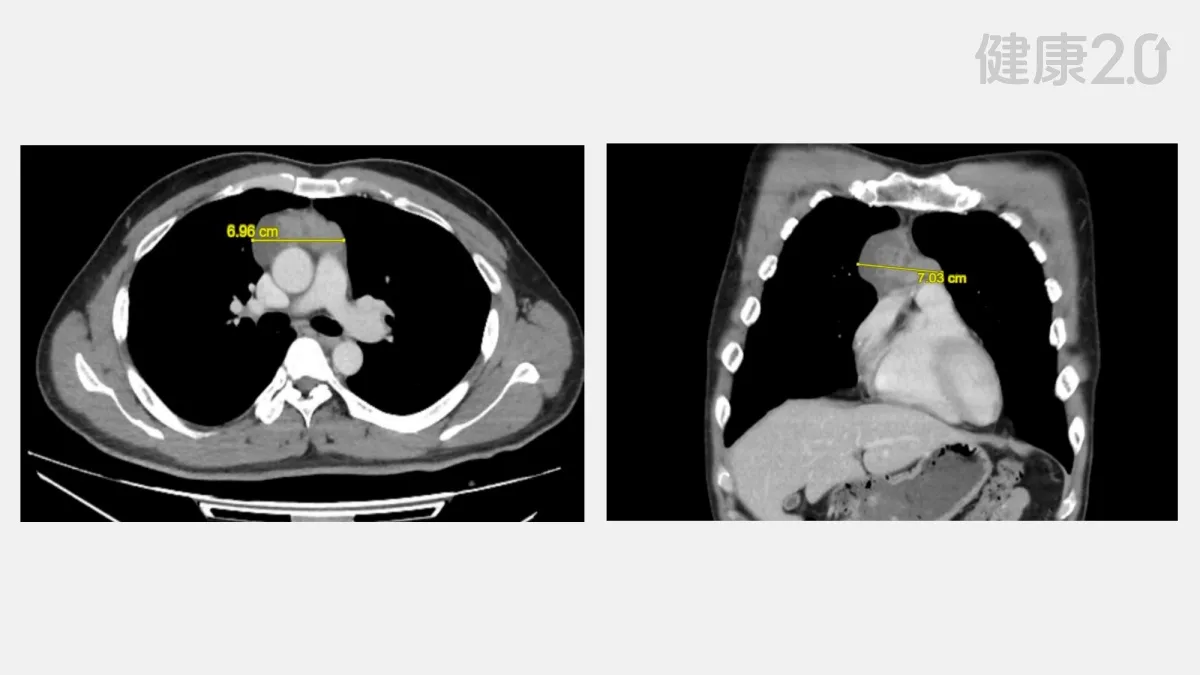

因為符合國民健康署的低劑量胸部電腦斷層掃描(LDCT)篩檢資格,68歲的陳先生前往仁愛長庚合作聯盟醫院接受肺癌篩檢。沒想到竟意外在縱膈腔內發現一顆約7公分的大腫瘤。

陳先生很驚訝,因為他沒有任何胸悶、咳嗽或呼吸困難等症狀,仁愛長庚合作聯盟醫院放射診療科莊芝林主任指出,影像學檢查已顯示這顆腫瘤極可能是胸腺瘤。他說,這類腫瘤若不即時處理,可能壓迫心臟、氣管等重要器官,後果不堪設想。